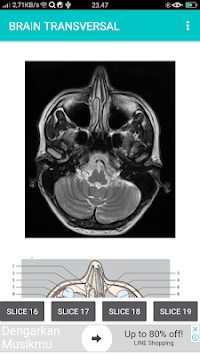

SECTIONAL ANATOMY MRI

POCKET ATLAS MRI is developed by Multirez and is available for free on the Google Play Store. POCKET ATLAS MRI has 5000 installations so far, with a required Android version of 4.0 and up. SECTIONAL ANATOMY MRI

Screenshots